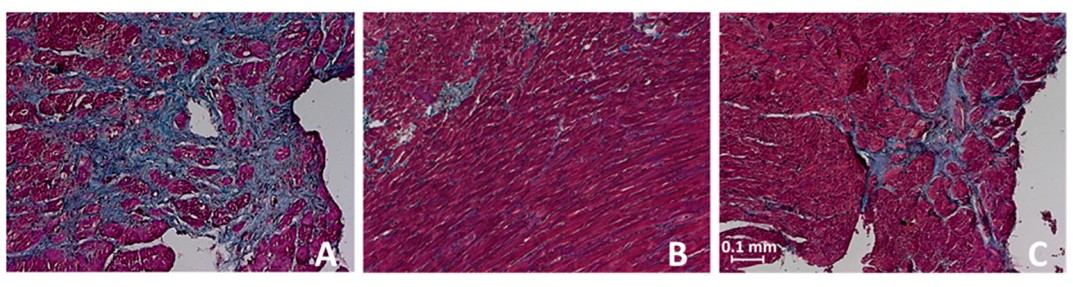

Fig.2 Hearts of untreated control and treated SHR in trichrome staining.2,3

In this study, researchers investigated the efficacy of late-onset antihypertensive treatment in old SHRs. The project results demonstrated that while significantly lower blood pressure values were achieved in young SHRs with shorter treatment periods, late-onset therapy in old SHRs also effectively reduced blood pressure and mitigated the development of cardiac damage. Notably, cardiac fibrosis was significantly attenuated only in young SHRs, emphasizing the critical importance of early intervention in hypertension management.